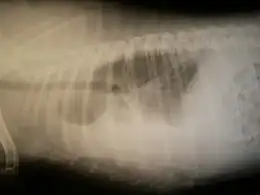

Radiographie

Une radiographie des poumons, de face et de profil, permet de faire le diagnostic en permettant de visualiser l'épanchement pleural.

Elle montre une opacité basale en nappe effaçant la coupole diaphragmatique et les culs de sac costo-diaphragmatiques.

Quand l'épanchement est très abondant, l'opacité recouvre tout l'hémithorax, refoule le médiastin du côté opposé. Quand il est peu abondant, l'opacité se limite à un comblement du cul-de-sac pleural inférieur.